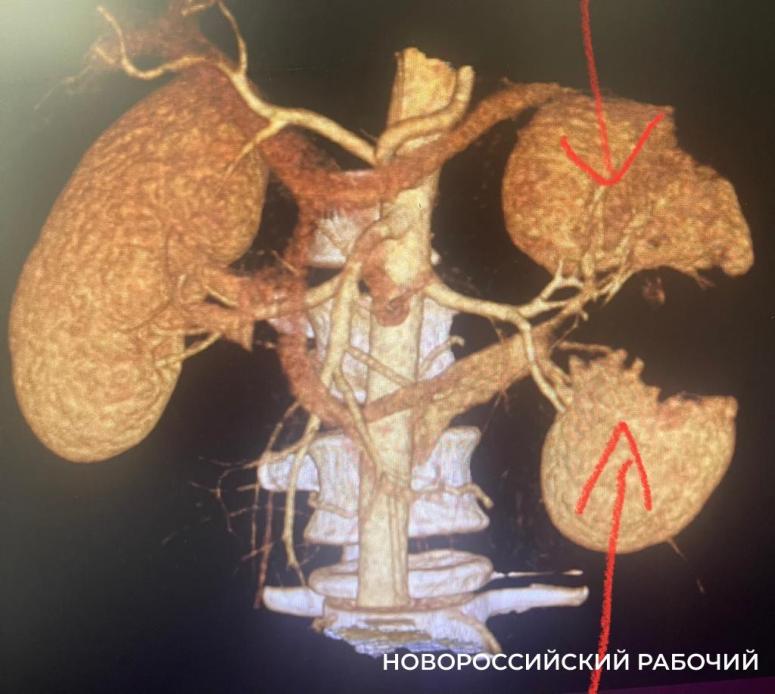

В горбольницу № 1 молодого человека доставила бригада «скорой помощи». Он находился в очень тяжелом состоянии: обследование показало, что левая почка от удара при падении была разорвана надвое, началось забрюшинное кровотечение.

Восстановить пострадавший орган было невозможно, его пришлось удалить. Операция длилась несколько часов. Она прошла успешно. Пациент поправляется и уже готовится к выписке, сообщает «Новороссийский рабочий».